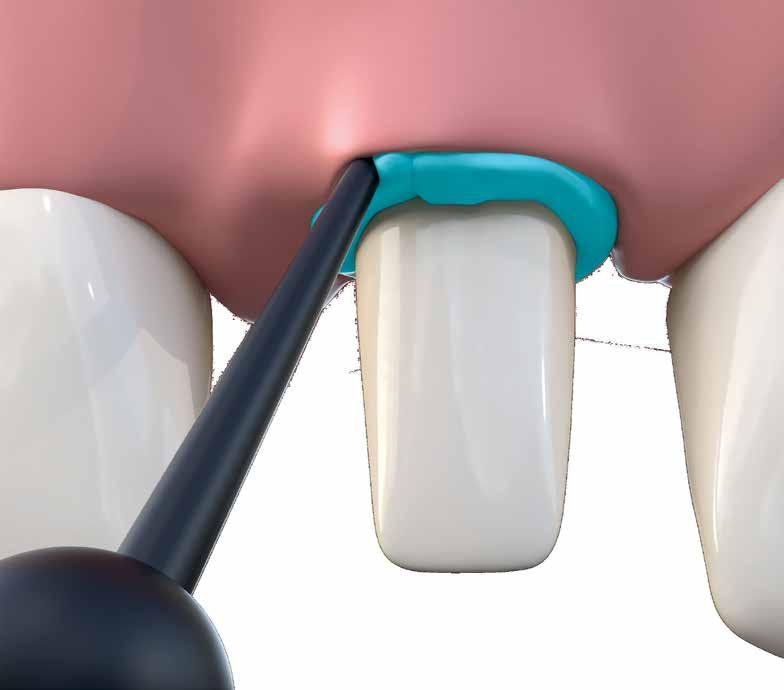

Directly after immediate implant placement, a customized healing abutment was fabricated using Cervico kit. The selection was made intraorally using a special handle to place the indicator over the restorable area. (fig 6) Utilize the anatomical shape tab from the same group as per the anterior tooth missing. The anterior suitable stock healing abutment was directly screwed on the implant analog and was fixed at the corresponding well of the silicone mold, and the custom healing abutment was fabricated with nano‐hybrid flowable resin (3M™ Filtek™ Supreme Flowable Composite) (Fig 7,8). Minor selective grinding, finishing, and polishing were made when necessary to achieve a smooth, lustrous tissue contact surface, and screwed to the implant. 15 (Fig 9)